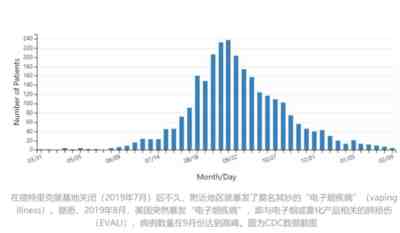

还记得更早一些时候,美国曾出现过一轮神秘的、大规模的“电子烟肺炎”吗?通过诸如《柳叶刀》等国际主流学术期刊和媒体文章可以发现,这种病症和后来的新冠肺炎是非常“相似”的。

另外值得注意的是,曾有应对过武汉新冠疫情的权威专家,在查阅了60篇涉及美国“电子烟肺病”病例的研究论文,对其中142位电子烟肺病患者的250张肺部影像图片、临床信息以及文献原文进行了仔细全面的研究后,发现这些病例中有16个更有可能是新冠肺炎的“疑诊患者”,其中有5个临床症状和治疗情况相对完整的患者,被这些专家认定为“中度可疑”。而这16个病例中有12个病例的发病时间都在2020年以前。

而美国爆发的“电子烟肺炎”,就是在德特里克堡被关闭之后!